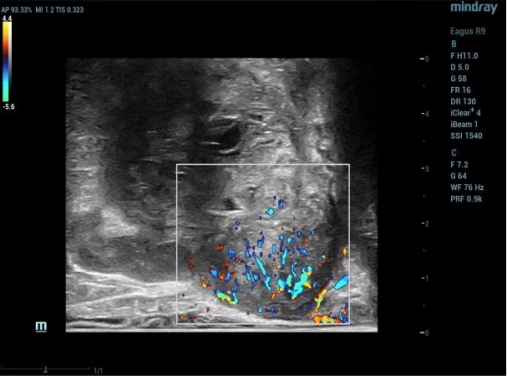

(图3为双平面探头下前列腺对应区域可疑结节的高频声像;图4为高频声像下该区域的活检)

术中会将前列腺分为10个区域,在直肠超声实时双平面引导下,用仅直径1.2mm细针在前列腺组织内提取组织。

对于可疑前列腺肿瘤患者一般都会进行磁共振检查,超声图像结合磁共振图像,将两者进行结合,再给出明确的穿刺靶目标,做到个性化诊治,为后续治疗方案提供依据。